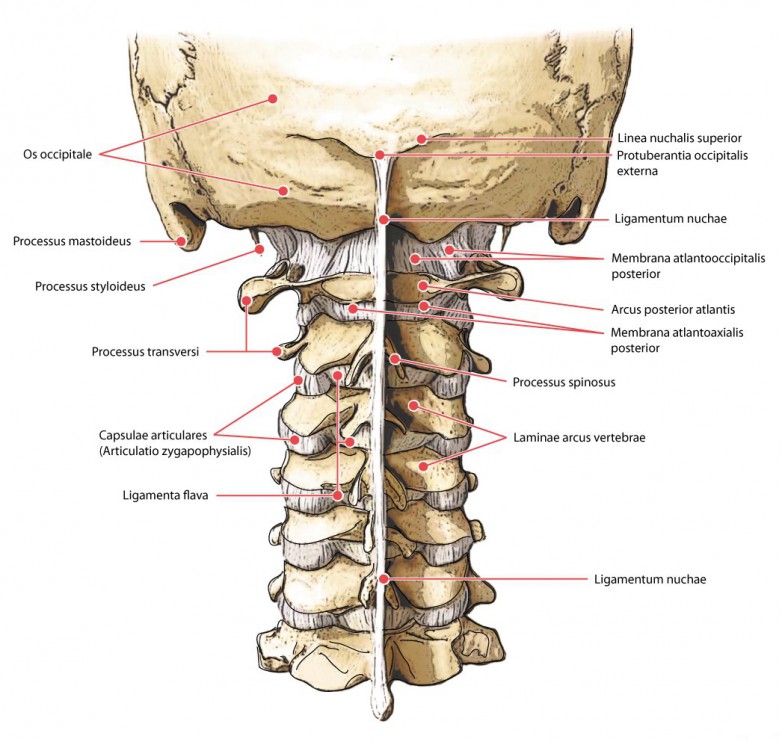

Obr. 1: Struktury krční páteře (zdroj: http://www.ehrlich.tv/halswirble-schaedel.jpg)

Krční páteř je velmi namáhanou oblastí vzhledem k její velké mobilitě oproti ostatním úsekům páteře. V souvislosti s bolestmi hlavy se jedná zejména o horní úsek krční páteře, první dva krční obratle, na které nasedá těžká lebka. Právě v úseku nazvaném antlantooccipitální skloubení (AO skloubení), spojení atlasu (první krční obratel) a lebky (záhlaví latinsky occiput), dochází k častým blokádám nejčastěji při dlouhodobé nevhodné poloze hlavy, kdy je hlava v předsunutém držení zároveň s mírným záklonem záhlaví. Blokády můžeme nalézat i v nižších úsecích krční páteře až po CTh přechod, ale ne vždy je v tomto úseku přítomný zjevný blok.